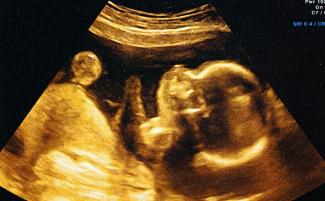

Ak je ultrazvuková technológia často oslavovaná západnými zástancami života, pretože dokazuje ľudskosť nenarodených detí, v Indii má aj svoju temnú stránku. Jej použitie na odhalenie pohlavia nenarodeného dieťaťa je nezákonné, pretože môže viesť k potratom s výberom pohlavia.

Podľa správy, ktorú v roku 2021 zverejnil Advokát pre verejné zdravie z univerzity v Berkeley’, “Feticida žien na základe testovania na určenie pohlavia… prudko vzrástla v Indii približne v 90. rokoch 20. storočia, keď sa ultrazvuková technológia rozšírila medzi príslušníkmi vyšších tried a vyšších kást spoločnosti.”

Indická vláda na tento prudký nárast reagovala zákazom tejto praxe prostredníctvom Zákona o technikách pred počatím a prenatálnej diagnostike z roku 1994, ale používanie ultrazvuku na potraty s výberom pohlavia pokračovalo aj napriek zákonu, čiastočne z dôvodu hlbokých a trvalých kultúrnych preferencií pre mužské deti.